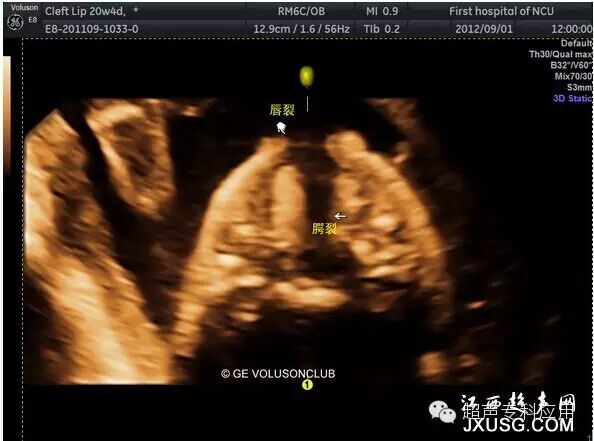

1.6 胎儿上腭的三维超声成像 对于唇裂胎儿,产前往往需要评估上腭的情况,以咨询双亲。有文献报道了利用三维重建面部反观冠状平面检查胎儿上腭,发现诊断唇裂的敏感性为95%,假阳性率7.7%;上牙槽裂的敏感性为84.5%,假阳性率7.2%;硬腭裂的敏感性89.7%,假阳性率15.6%。

胎儿唇腭裂三维成像-右下角三维冠状面显示腭裂

胎儿唇腭裂三维容积对比成像重建显示上腭